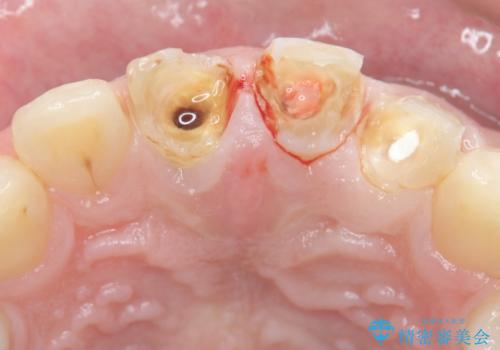

- 前歯の変色や形態を含む、見た目を改善したいと希望され来院されました。

視診・X線検査・歯周組織検査より下記のような問題が列挙され、長期的な予後を見込むために一つづつ問題の解決を計ります。

・不十分な根管治療 →マイクロスコープを用いる精密根管医療

・歯の変色 →ジルコニアクラウンの製作

・歯肉縁下カリエス →部分矯正による歯の挺出・歯周外科